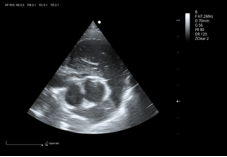

8P2MA ● 3.5-15.0MHz ● Single crystal phased array probe ● For Cardiology of felines |

3P2PA ● 1.0-6.5MHz ● Phased array probe ● For Cardiology of big-sized canines |

5P1PAA ● 2.5-13.0MHz ● Phased array probe ● For Cardiology of small and medium-sized canines |